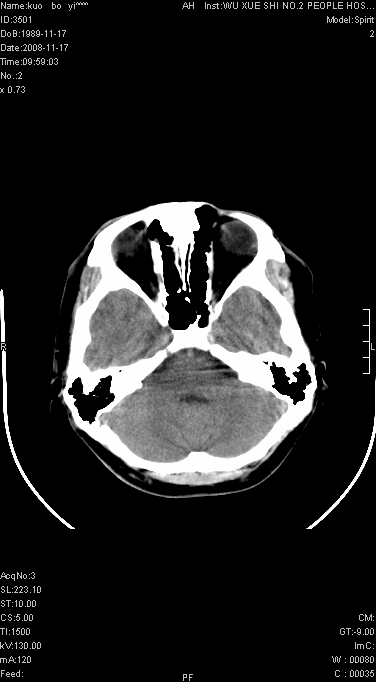

增强已传.年龄19岁.请会诊

增强后水肿中心高密度灶有明显强化,强化不均匀,呈雪花状或絮状,且强化明显,若为肿瘤,应该出现形态较规则的瘤体影,强也有例外如胶质瘤就可以形态不规则.但胶质瘤明显强化者多为恶性间变性,与病史及相关表现太不相符.因此本例多考虑为炎症引起.

左顶叶较大范围水肿区,内见明显强化的片状 棉絮状组织,但占位效应不明显。多考虑:脑炎!

还是考虑原发脑胶质瘤,梗塞缺血水肿的低密度要同时累及皮、髓质并要符合动脉供血的区域分界特点,本例强化后见瘤体结节及向周围浸润生长的瘤血管都强化了,水肿广泛呈指状,占位效应使同侧脑皮质受压变薄、脑沟消失但因实质性的瘤体尚小所以中线无明显移位。不知各位同意这样分析吗?(转移瘤多为多处病灶)

首先考虑脑胶质瘤。有明显的左顶叶脑白质水肿,病变轻度占位效应,花环样强化,脑炎——影像不支持!